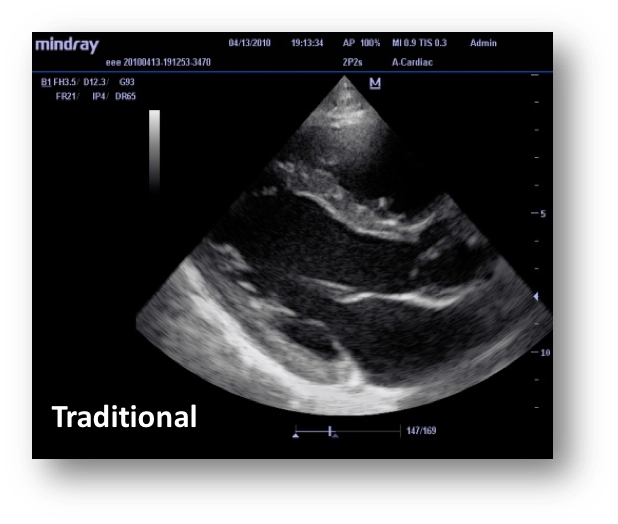

Разберем наглядно разницу в изображении датчиков с применением технологии 3T:

26.png